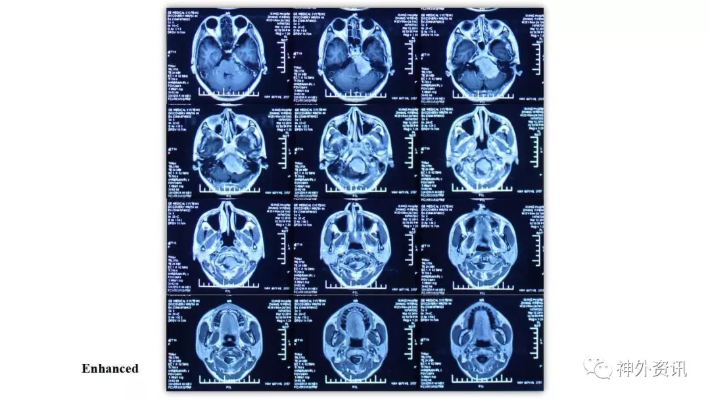

经乙状窦后联合远外侧入路切除岩斜-枕骨大孔-颈2脑膜瘤一例